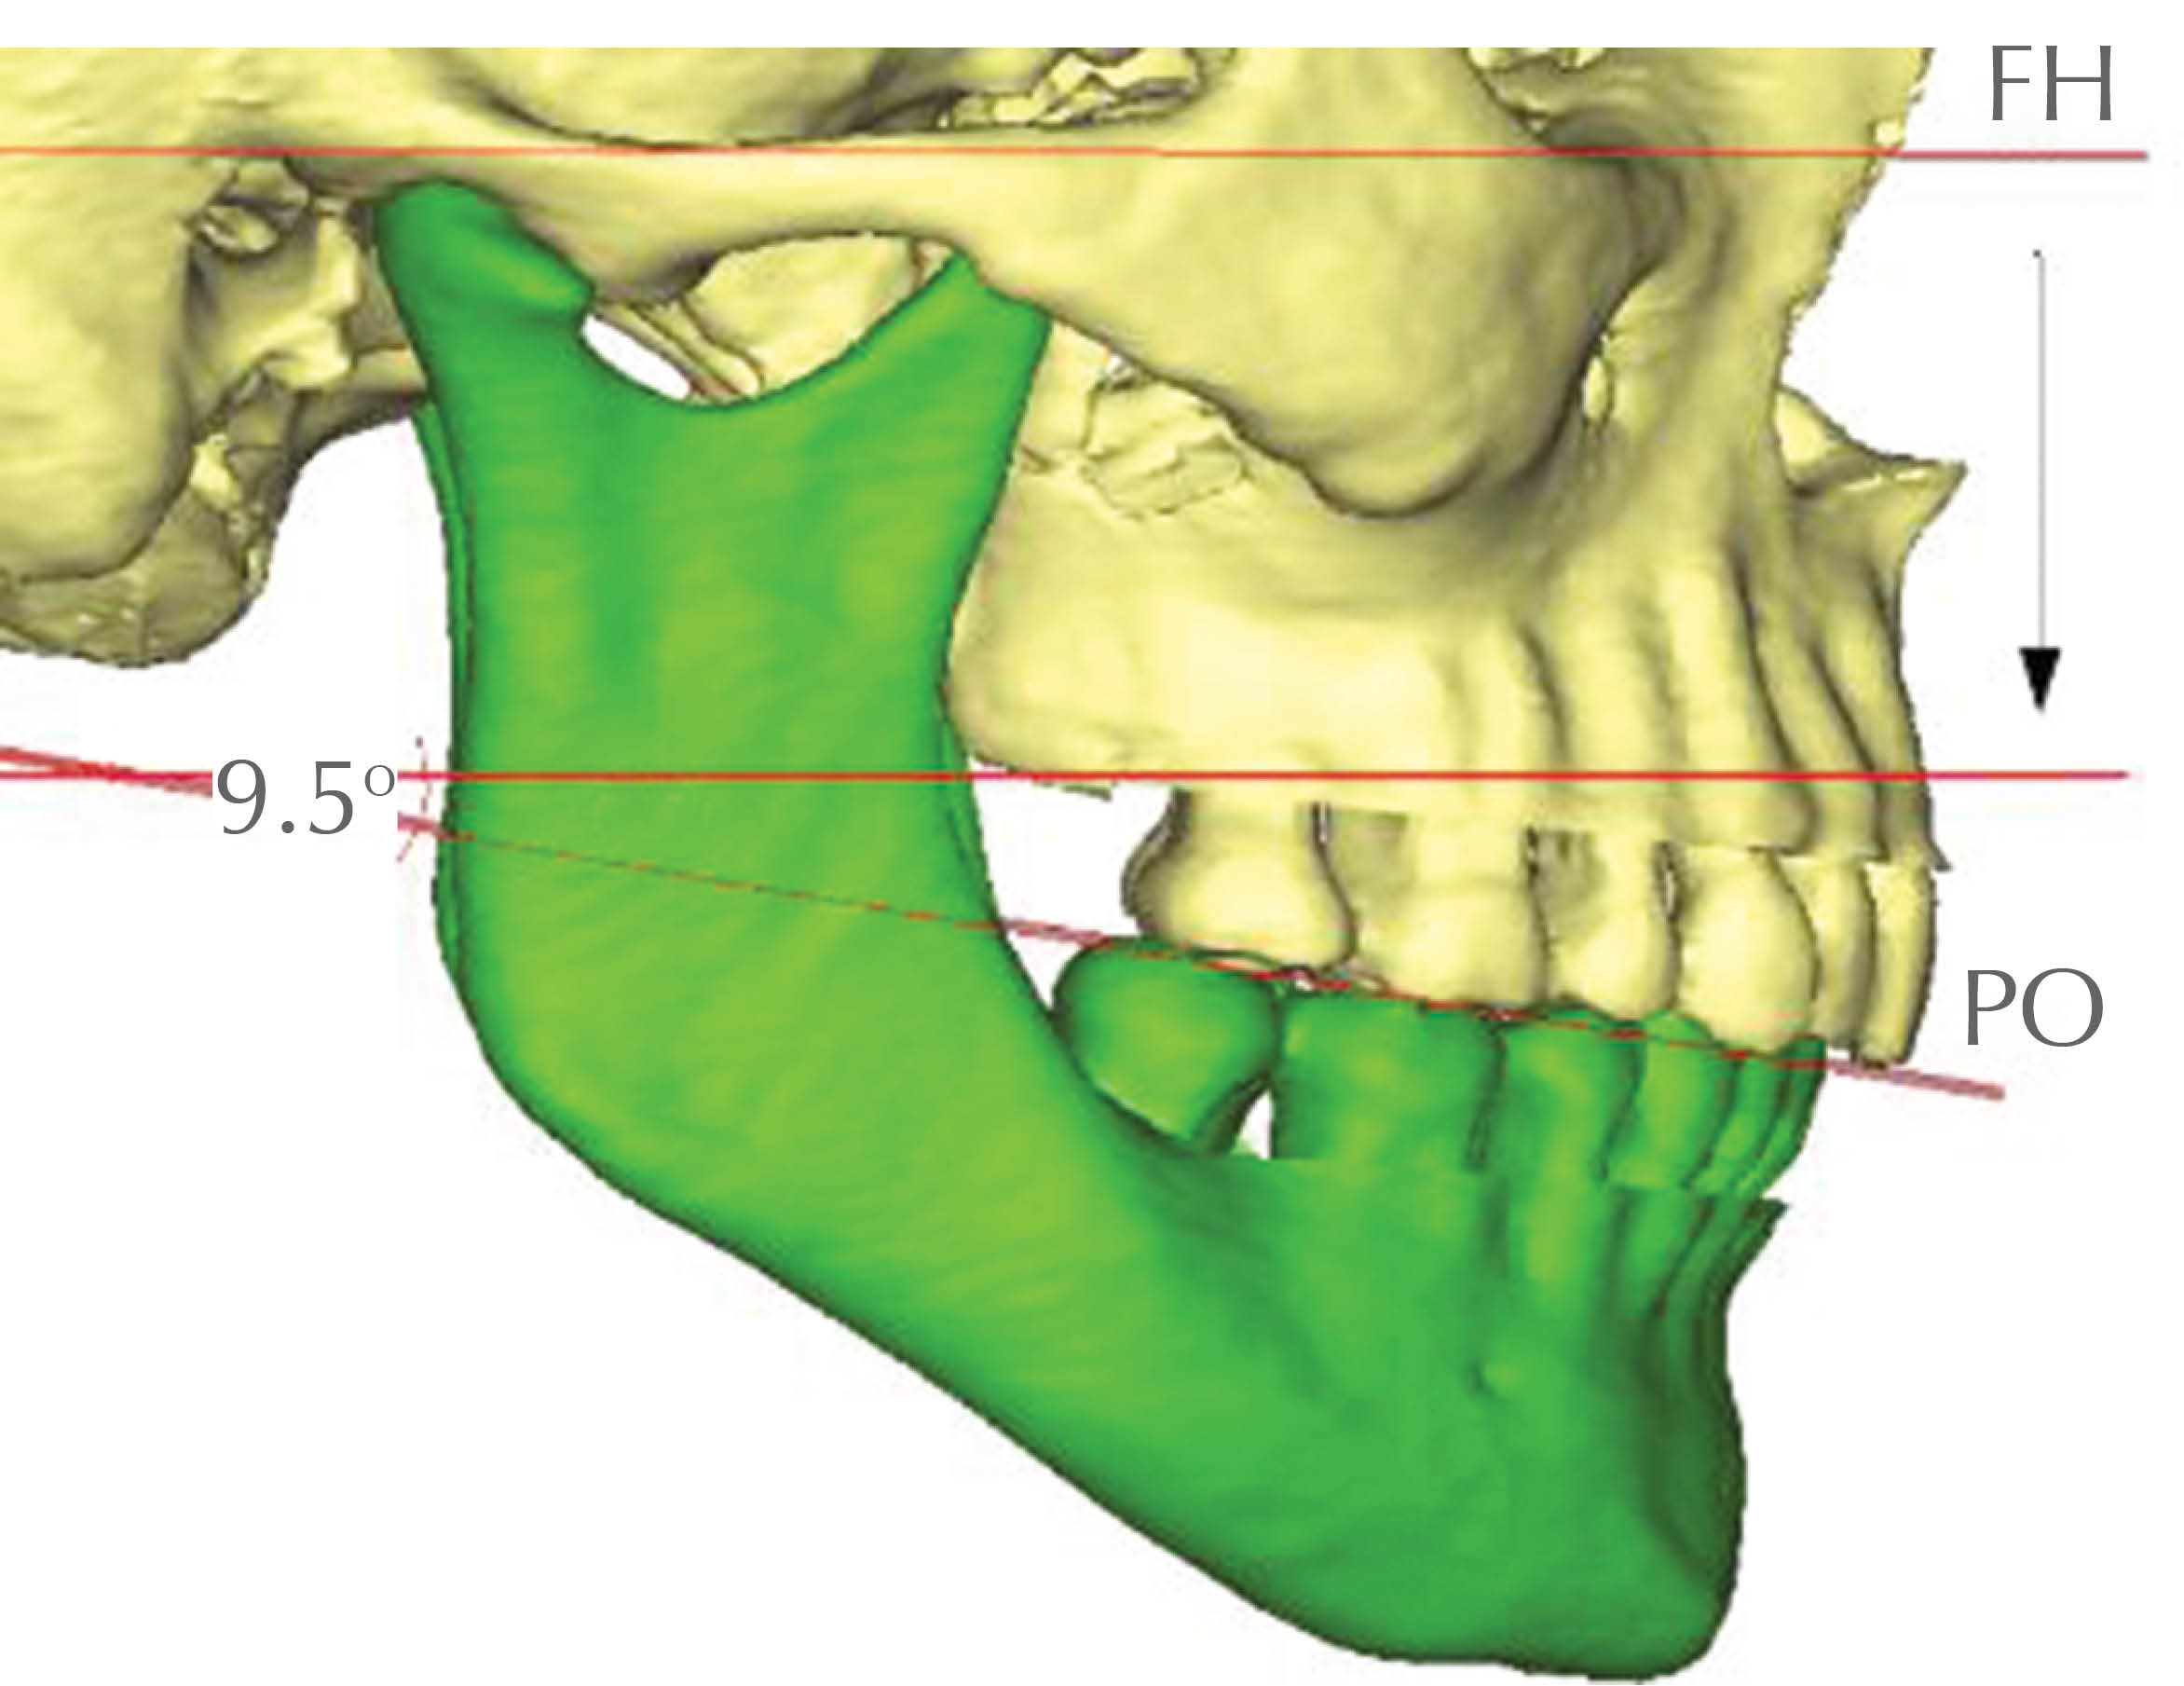

• 32. PO-FH: ángulo del plano oclusal del maxilar superior; ángulo formado por la intersección del plano oclusal (plano determinado por el borde de los incisivos superiores y las cúspides mesiovestibulares de los primeros molares superiores) y el plano de Frankfurt (Figura 37).

Figura 38